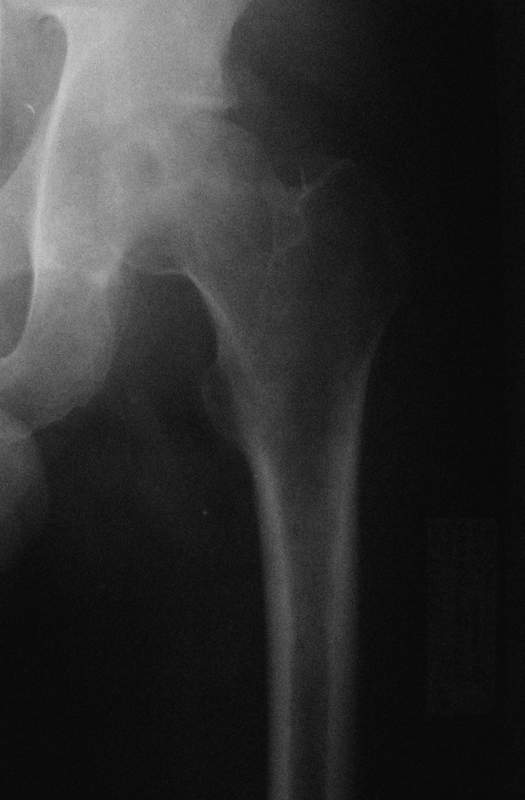

Молодой человек, 37л. Начало заболевания сентябрь 2007, резкие боли в области лев. тазобедренного сустава, повышение температуры до 39 гр., в течение недели, лабораторные данные: лейкоцитоз со сдвигом влево. Посев крови на стерильность возбудителя не выявил. По данным Рг, РКТ выставлен диагноз: Левосторонний коксит? Асептический некроз? Проводилось лечение: цефсон в/в неделю, иммобилизация кокситной повязкой 1 мес. Обратился повторно 10 дней назад с жалобами на сильные боли в левом тазобедренном суставе, белая кровь – нормограмма, СОЭ 46 мм/ч. На сегодняшний день: болей не отмечает. Лаб.данные: белая кровь – нормограмма, СОЭ 30 мм/ч. Рентген и РКТ прилагаем.

Уважаемый коллега! Судя по представленной скромной информации у больного, вероятней всего, речь идет о банальном коксите с преимущественной очаговой деструкцией проксимального эпифиза бедренной кости. Учитывая возраст пациента, течение заболевания, эффект от проведенной Вами терапии больному показана радикально-пластическая операция в объеме некрэктомии и пластики головки бедренной кости с последующей рациональной функциональной реабилитацией сустава в условиях разгрузки. Гисто- и бакисследование материала поможет быстее верифицировать процесс.

Мне представляется, что предоставлен случай аваскулярного некроза головки бедра. Для определения тактики лечения необходимо выполнить ренгенограммы лучшего качества и посмотреть все срезы на уровне головки. Предоставленные срезы -уровень ямки,т.е. малонагружаемой зоне, наличие в этой зоне участков сегментарного некроза скорее всего не приведет к деформации головки, при таком варианте разгрузка конечности на 3-4 мес может привести к благоприятному исходу.

При наличии участков некроза внутри головки близко к нагружаемой зоне для профилактики имперссионного прелома, вероятно, целесообразно выполнить Core Decompression (тема обсуждалась на форуме). В случае расположения участков некроза, затрагивающих суставную поверхность в нагружаемой зоне может быть целесообразным выполнение операций на проксимальном отделе бедра, ставящих целью выведение участков некроза из под нагрузки. Ну и протезирование, конечно, как вариант.